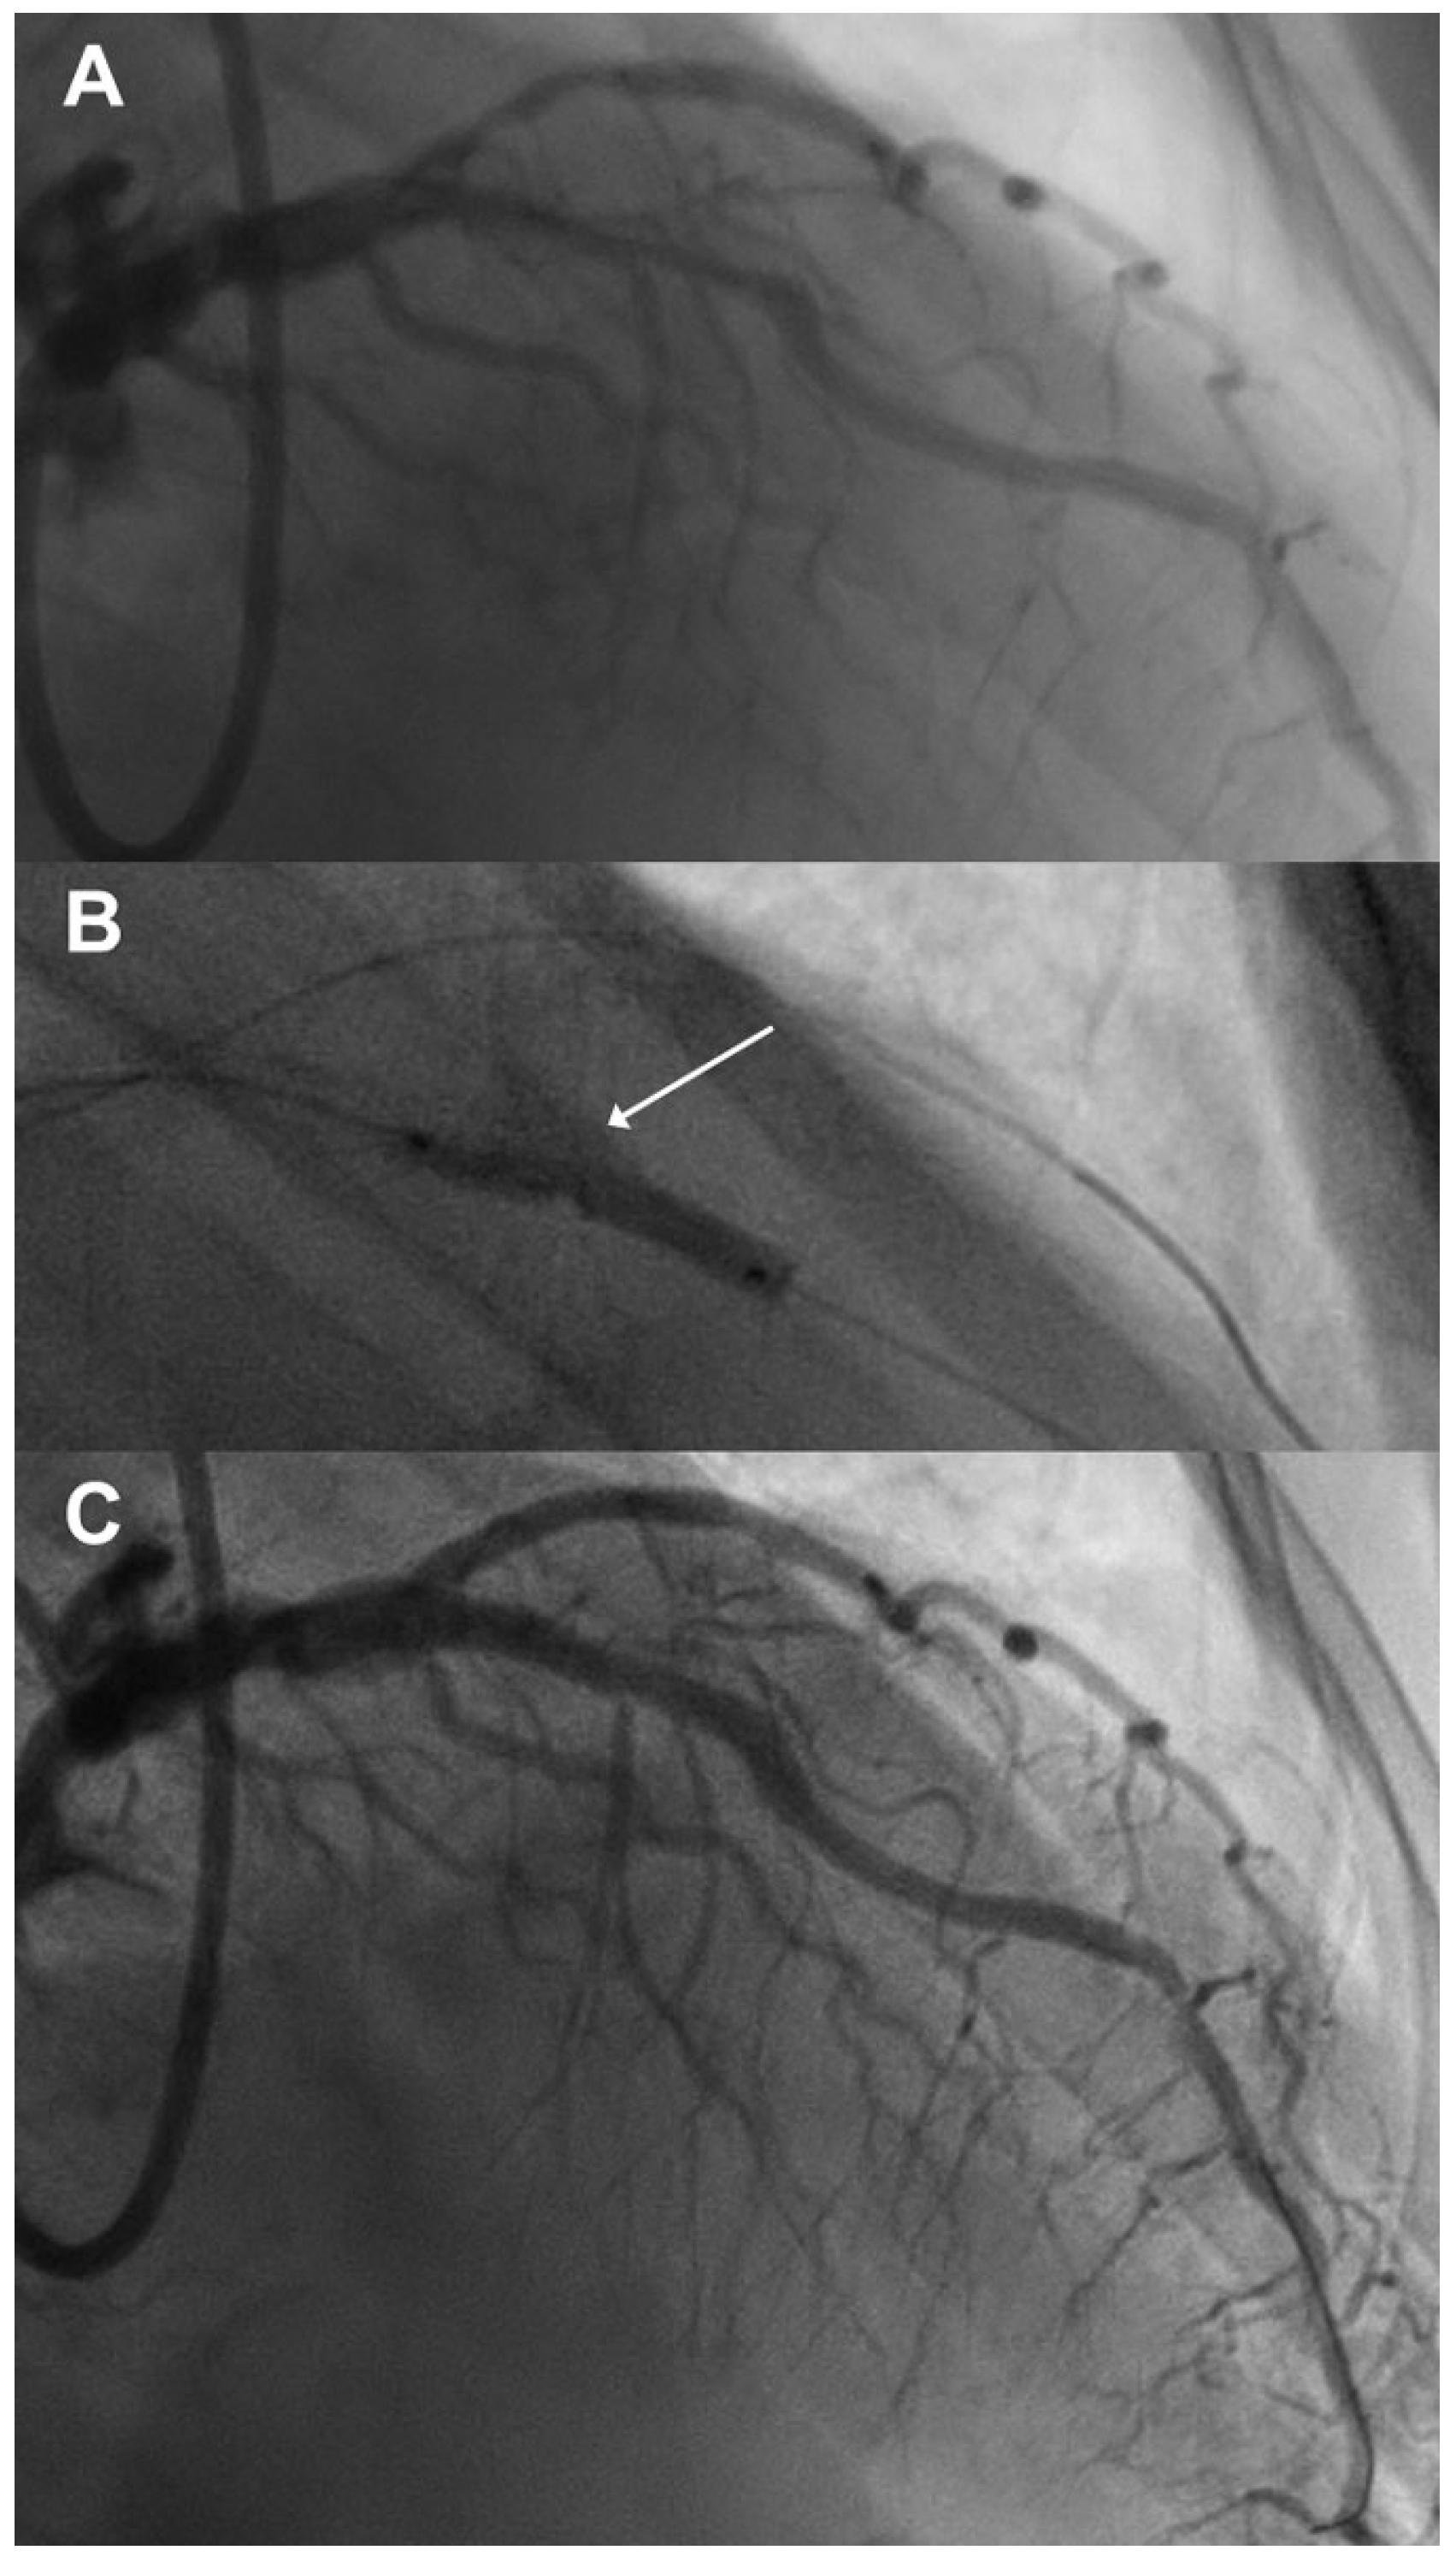

A 79-year-old gentleman with a known history of diabetes and arterial hypertension was diagnosed with non-ST-elevation myocardial infarction (NSTEMI) on the basis of typical chest pain at rest, anterior ST depression on the ECG and mildly elevated troponin T (450 ng/ml). He underwent urgent coronary angiography, where a heavily calcified bifurcation stenosis of the left anterior descending artery (LAD) and the diagonal branch was seen (Figure 1A). After discussion, the heart team settled on a percutaneous strategy. The patient was pretreated with aspirin, ticagrelor, atorvastatin and unfractionated heparin, and underwent a percutaneous coronary intervention (PCI) two days after coronary angiography.

The LAD and the diagonal branch were dilated with a 2.5-mm regular noncompliant balloon at 14 atm to enable optical coherence tomography (OCT) and assessment of the extent and distribution of the angiographically visible calcium. Of note, the noncompliant balloon expanded incompletely, which emphasised the lesion’s anticipated degree of calcification, as depicted in Figure 1B (arrow). The subsequent OCT run confirmed the prevalence of extensive circular calcium (Figure 2A). After predilatation, OCT indicated a minimum lumen area of 2.82 mm2 within the treated segment. Based on those findings, we decided to use intravascular lithoplasty to optimally prepare the calcified lesion for stent implantation. A 3.0-mm balloon (Shockwave Medical, Fremont, California) was used at 4 atm to deliver six pulses. The OCT investigation after lithoplasty demonstrated calcium cracks in the intima and the media of the LAD (minimum lumen area 3.09 mm2) (Figure 2B). A 2.25 × 23 mm everolimus-eluting stent was placed in the diagonal branch and a 3.0 × 33 mm everolimus-eluting stent was implanted in the LAD with use of the mini-crush technique. The LAD was then postdilated using a 3.5-mm noncompliant balloon at 16 atm followed by a final kissing balloon inflation (3.5-mm noncompliant balloon in the LAD and 2.5-mm noncompliant balloon in the diagonal branch). A good final angiographic result was achieved (Figure 1C). The next OCT demonstrated good expansion and apposition of the stent (minimum luminal area 5.38 mm2, stent expansion index 0.81) (Figure 2C–E). Since there was some malapposition within very proximal/ostial stent segment (21 struts with >300µm) (arrow, Figure 2E), a proximal optimisation procedure using a 4.0-mm noncompliant balloon was additionally performed. The patient was discharged home 2 days later. He is in good condition and free of any cardiac symptom 4 months after the procedure.

Figure 1. (A) Initial angiogram indicating a heavily calcified proximal to mid left anterior descending artery stenosis; (B) incomplete expansion (arrow) of the 2.5-mm noncompliant balloon; (C) final angiogram after stenting.